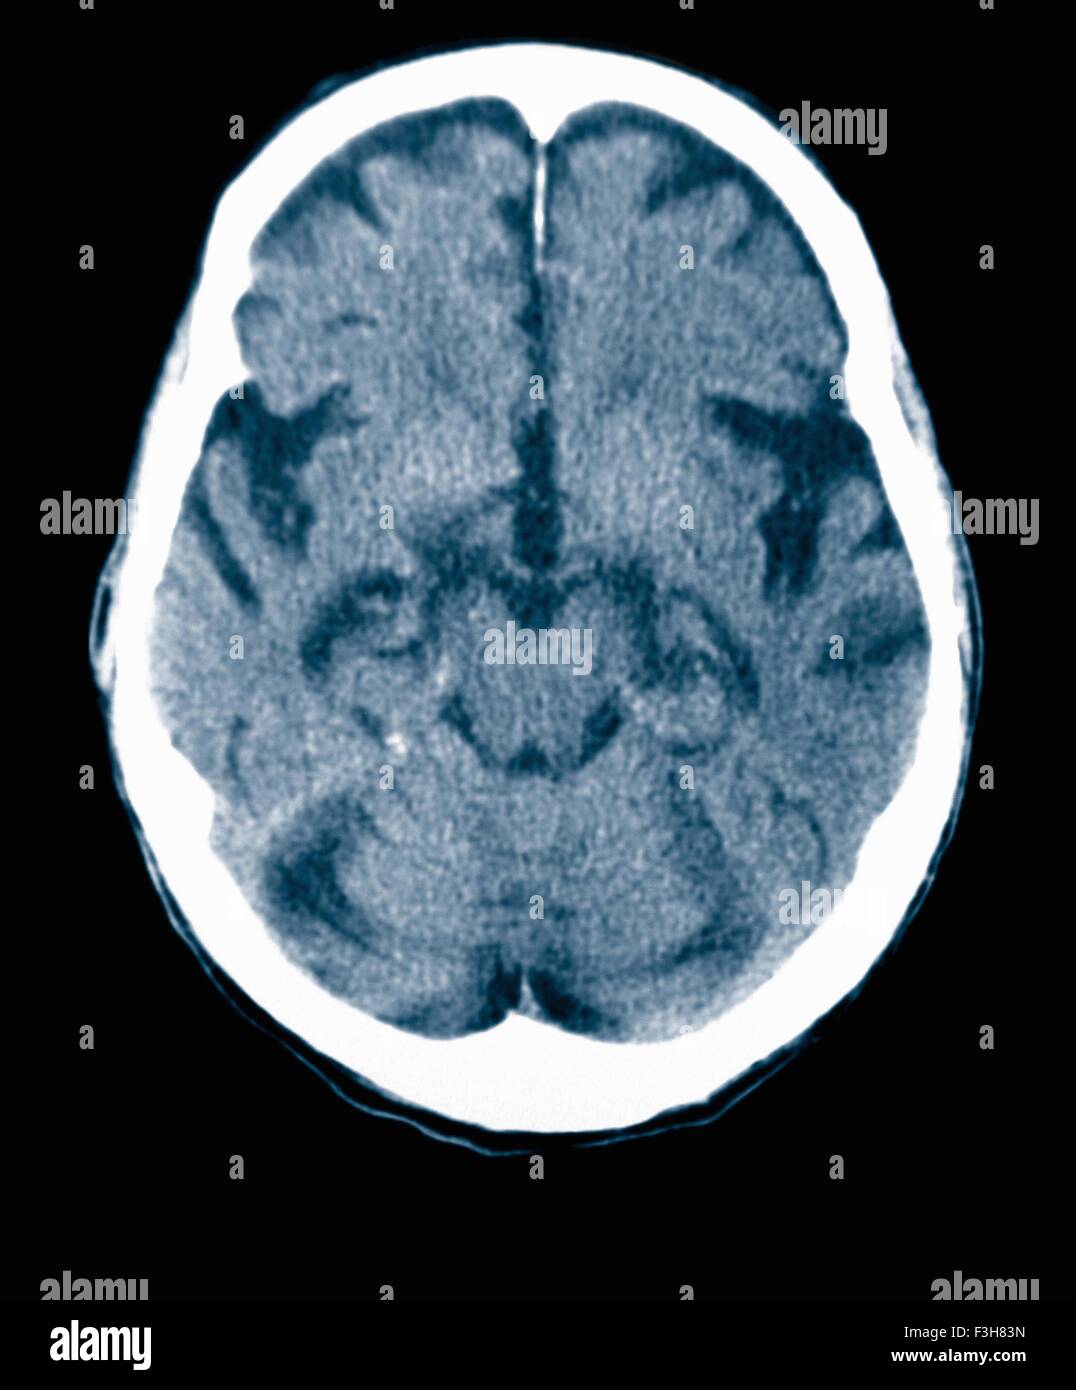

CT scan 84 ans homme à la maladie d'Alzheimer. La TDM montre l'atrophie du cerveau avec de petites et grandes circonvolutions sulci Banque D'Imageshttps://www.alamyimages.fr/image-license-details/?v=1https://www.alamyimages.fr/photo-image-ct-scan-84-ans-homme-a-la-maladie-d-alzheimer-la-tdm-montre-l-atrophie-du-cerveau-avec-de-petites-et-grandes-circonvolutions-sulci-88275359.html

CT scan 84 ans homme à la maladie d'Alzheimer. La TDM montre l'atrophie du cerveau avec de petites et grandes circonvolutions sulci Banque D'Imageshttps://www.alamyimages.fr/image-license-details/?v=1https://www.alamyimages.fr/photo-image-ct-scan-84-ans-homme-a-la-maladie-d-alzheimer-la-tdm-montre-l-atrophie-du-cerveau-avec-de-petites-et-grandes-circonvolutions-sulci-88275359.htmlRFF3H83B–CT scan 84 ans homme à la maladie d'Alzheimer. La TDM montre l'atrophie du cerveau avec de petites et grandes circonvolutions sulci

CT scan 84 ans homme à la maladie d'Alzheimer. La TDM montre l'atrophie du cerveau avec de petites et grandes circonvolutions sulci Banque D'Imageshttps://www.alamyimages.fr/image-license-details/?v=1https://www.alamyimages.fr/photo-image-ct-scan-84-ans-homme-a-la-maladie-d-alzheimer-la-tdm-montre-l-atrophie-du-cerveau-avec-de-petites-et-grandes-circonvolutions-sulci-88275360.html

CT scan 84 ans homme à la maladie d'Alzheimer. La TDM montre l'atrophie du cerveau avec de petites et grandes circonvolutions sulci Banque D'Imageshttps://www.alamyimages.fr/image-license-details/?v=1https://www.alamyimages.fr/photo-image-ct-scan-84-ans-homme-a-la-maladie-d-alzheimer-la-tdm-montre-l-atrophie-du-cerveau-avec-de-petites-et-grandes-circonvolutions-sulci-88275360.htmlRFF3H83C–CT scan 84 ans homme à la maladie d'Alzheimer. La TDM montre l'atrophie du cerveau avec de petites et grandes circonvolutions sulci

CT scan 84 ans homme à la maladie d'Alzheimer. La TDM montre l'atrophie du cerveau avec de petites et grandes circonvolutions sulci Banque D'Imageshttps://www.alamyimages.fr/image-license-details/?v=1https://www.alamyimages.fr/photo-image-ct-scan-84-ans-homme-a-la-maladie-d-alzheimer-la-tdm-montre-l-atrophie-du-cerveau-avec-de-petites-et-grandes-circonvolutions-sulci-88275369.html

CT scan 84 ans homme à la maladie d'Alzheimer. La TDM montre l'atrophie du cerveau avec de petites et grandes circonvolutions sulci Banque D'Imageshttps://www.alamyimages.fr/image-license-details/?v=1https://www.alamyimages.fr/photo-image-ct-scan-84-ans-homme-a-la-maladie-d-alzheimer-la-tdm-montre-l-atrophie-du-cerveau-avec-de-petites-et-grandes-circonvolutions-sulci-88275369.htmlRFF3H83N–CT scan 84 ans homme à la maladie d'Alzheimer. La TDM montre l'atrophie du cerveau avec de petites et grandes circonvolutions sulci

CT scan 84 ans homme à la maladie d'Alzheimer. La TDM montre l'atrophie du cerveau avec de petites et grandes circonvolutions sulci Banque D'Imageshttps://www.alamyimages.fr/image-license-details/?v=1https://www.alamyimages.fr/photo-image-ct-scan-84-ans-homme-a-la-maladie-d-alzheimer-la-tdm-montre-l-atrophie-du-cerveau-avec-de-petites-et-grandes-circonvolutions-sulci-88275367.html

CT scan 84 ans homme à la maladie d'Alzheimer. La TDM montre l'atrophie du cerveau avec de petites et grandes circonvolutions sulci Banque D'Imageshttps://www.alamyimages.fr/image-license-details/?v=1https://www.alamyimages.fr/photo-image-ct-scan-84-ans-homme-a-la-maladie-d-alzheimer-la-tdm-montre-l-atrophie-du-cerveau-avec-de-petites-et-grandes-circonvolutions-sulci-88275367.htmlRFF3H83K–CT scan 84 ans homme à la maladie d'Alzheimer. La TDM montre l'atrophie du cerveau avec de petites et grandes circonvolutions sulci

CT scan d'un vieil homme de 84 ans souffrant de la maladie d'Alzheimer. La TDM montre l'atrophie du cerveau. Banque D'Imageshttps://www.alamyimages.fr/image-license-details/?v=1https://www.alamyimages.fr/photo-image-ct-scan-d-un-vieil-homme-de-84-ans-souffrant-de-la-maladie-d-alzheimer-la-tdm-montre-l-atrophie-du-cerveau-84989410.html

CT scan d'un vieil homme de 84 ans souffrant de la maladie d'Alzheimer. La TDM montre l'atrophie du cerveau. Banque D'Imageshttps://www.alamyimages.fr/image-license-details/?v=1https://www.alamyimages.fr/photo-image-ct-scan-d-un-vieil-homme-de-84-ans-souffrant-de-la-maladie-d-alzheimer-la-tdm-montre-l-atrophie-du-cerveau-84989410.htmlRMEX7GT2–CT scan d'un vieil homme de 84 ans souffrant de la maladie d'Alzheimer. La TDM montre l'atrophie du cerveau.

CT scan d'un vieil homme de 84 ans souffrant de la maladie d'Alzheimer. La TDM montre l'atrophie du cerveau. Banque D'Imageshttps://www.alamyimages.fr/image-license-details/?v=1https://www.alamyimages.fr/photo-image-ct-scan-d-un-vieil-homme-de-84-ans-souffrant-de-la-maladie-d-alzheimer-la-tdm-montre-l-atrophie-du-cerveau-84989393.html

CT scan d'un vieil homme de 84 ans souffrant de la maladie d'Alzheimer. La TDM montre l'atrophie du cerveau. Banque D'Imageshttps://www.alamyimages.fr/image-license-details/?v=1https://www.alamyimages.fr/photo-image-ct-scan-d-un-vieil-homme-de-84-ans-souffrant-de-la-maladie-d-alzheimer-la-tdm-montre-l-atrophie-du-cerveau-84989393.htmlRMEX7GRD–CT scan d'un vieil homme de 84 ans souffrant de la maladie d'Alzheimer. La TDM montre l'atrophie du cerveau.

CT scan d'un vieil homme de 84 ans souffrant de la maladie d'Alzheimer. La TDM montre l'atrophie du cerveau. Banque D'Imageshttps://www.alamyimages.fr/image-license-details/?v=1https://www.alamyimages.fr/photo-image-ct-scan-d-un-vieil-homme-de-84-ans-souffrant-de-la-maladie-d-alzheimer-la-tdm-montre-l-atrophie-du-cerveau-84989418.html

CT scan d'un vieil homme de 84 ans souffrant de la maladie d'Alzheimer. La TDM montre l'atrophie du cerveau. Banque D'Imageshttps://www.alamyimages.fr/image-license-details/?v=1https://www.alamyimages.fr/photo-image-ct-scan-d-un-vieil-homme-de-84-ans-souffrant-de-la-maladie-d-alzheimer-la-tdm-montre-l-atrophie-du-cerveau-84989418.htmlRMEX7GTA–CT scan d'un vieil homme de 84 ans souffrant de la maladie d'Alzheimer. La TDM montre l'atrophie du cerveau.

CT scan d'un vieil homme de 84 ans souffrant de la maladie d'Alzheimer. La TDM montre l'atrophie du cerveau. Banque D'Imageshttps://www.alamyimages.fr/image-license-details/?v=1https://www.alamyimages.fr/photo-image-ct-scan-d-un-vieil-homme-de-84-ans-souffrant-de-la-maladie-d-alzheimer-la-tdm-montre-l-atrophie-du-cerveau-84989392.html

CT scan d'un vieil homme de 84 ans souffrant de la maladie d'Alzheimer. La TDM montre l'atrophie du cerveau. Banque D'Imageshttps://www.alamyimages.fr/image-license-details/?v=1https://www.alamyimages.fr/photo-image-ct-scan-d-un-vieil-homme-de-84-ans-souffrant-de-la-maladie-d-alzheimer-la-tdm-montre-l-atrophie-du-cerveau-84989392.htmlRMEX7GRC–CT scan d'un vieil homme de 84 ans souffrant de la maladie d'Alzheimer. La TDM montre l'atrophie du cerveau.